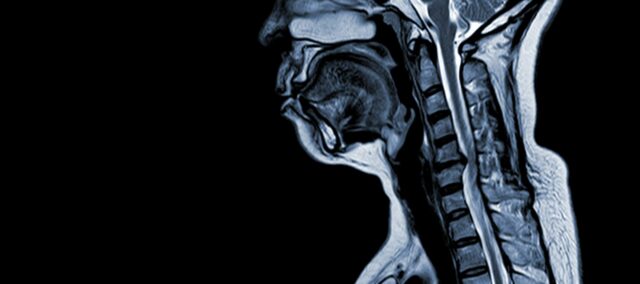

颈椎病(CSM)是一种神经系统疾病,是导致成人脊髓损伤的主要原因。 简单地说,就是颈部脊髓受到压迫或损伤,主要是由于颈椎的自然老化过程造成的。 脊髓病 "一词源于希腊语中的 "myelon"(意为 "脊髓")和 "pathos"(意为 "疾病")。

CSM 是一种复杂的病症,其病理生理学是由多种因素造成的,其中包括颈椎的结构变化。 有几个关键因素导致了这种疾病的发展和恶化:

- 椎间盘变性(椎间盘突出): CSM 通常始于颈椎椎间盘的退化,导致椎间盘凸出或突出到椎管内。

- 骨膜下骨形成(椎管内侧): 在机械压力增加的情况下,人体会在椎管前侧(腹侧)形成新的骨组织,从而可能缩小脊髓的空间。

- 后纵韧带骨化: 后纵韧带可能会发生骨化、硬化和钙化,导致椎管狭窄。

- 黄韧带肥厚: 黄韧带肥厚会导致其变粗,灵活性降低,进一步侵占椎管内的空间,压迫脊髓。

这些结构性变化共同导致椎管受压和狭窄,从而引起 CSM 的典型症状和并发症。 认识这些风险因素并了解其中的病理生理机制对于预防和管理都至关重要。 早期诊断和适当干预对于减轻这些结构性改变对脊髓的影响至关重要。